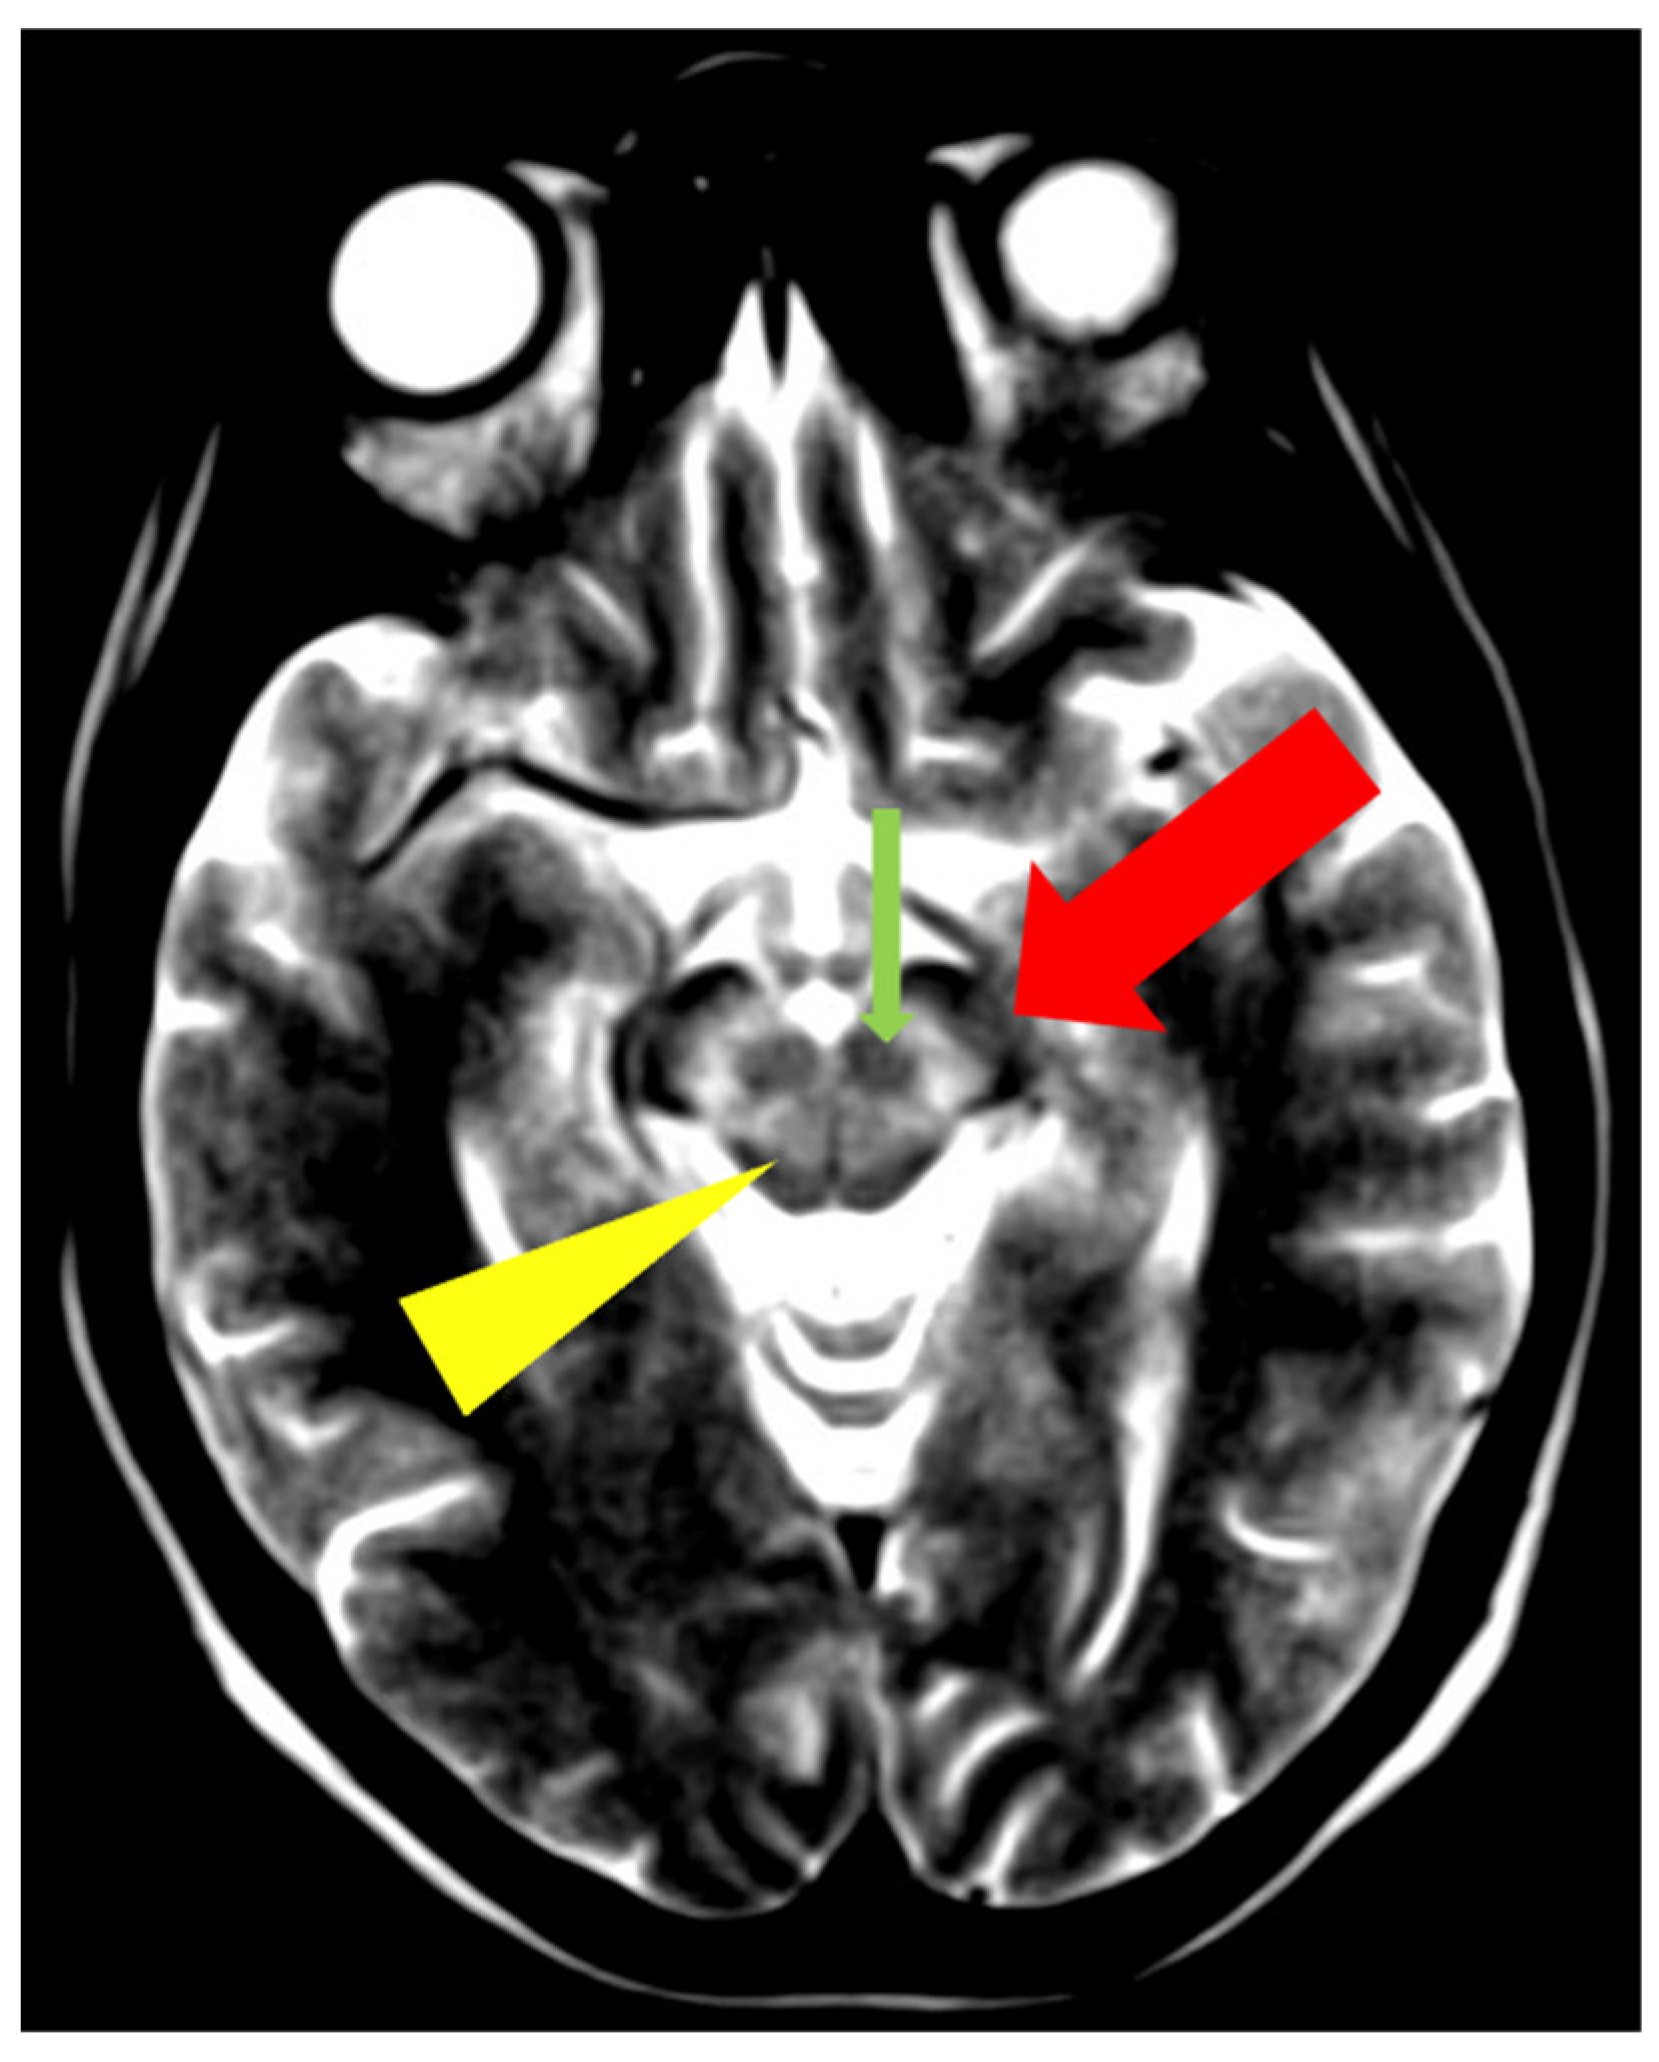

5. Neuroradiological Pathognomonic Signs of WD

- Rędzia-Ogrodnik, B.; Członkowska, A.; Antos, A.; Bembenek, J.; Kurkowska-Jastrzębska, I.; Przybyłkowski, A.; Skowrońska, M.; Smoliński, Ł.; Litwin, T. Pathognomonic neuroradiological signs in Wilson’s disease—Truth or myth? Park. Relat. Disord. 2023, 107, 105247. [Google Scholar] [CrossRef] [PubMed]

- Hitoshi, S.; Iwata, M.; Yoshikawa, K. Mid-brain pathology of Wilson’s disease: MRI analysis of three cases. J. Neurol. Neurosurg. Psychiatry 1991, 54, 624–626. [Google Scholar] [CrossRef] [PubMed]

- George, U.; Varte, N.; Rathore, S.; Jain, V.; Goyal, S. “Split thalamus”: Internal medullary involvement in Wilson’s disease. Neurol. India 2010, 58, 680. [Google Scholar] [CrossRef] [PubMed]

- Sener, R.N. The claustrum on MRI: Normal anatomy, and the bright claustrum as a new sign in Wilson’s disease. Pediatr. Radiol. 1993, 23, 594–596. [Google Scholar] [CrossRef] [PubMed]